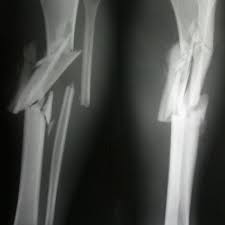

Spiral fractures are complete fractures of long bones that result from a rotational force applied to the bone. Summary summary (text) medline pmcid list. Spiral fractures are usually the result of high energy trauma and are likely to be associated with. Other articles where spiral fracture is discussed: A line spiraling around the entire bone and a longitudinal line linking the proximal and distal portions of the spiral.

Two spiral fractures sustained following only minor trauma. Complete fractures are categorized based on the way the bone breaks. It occurs due to a rotational, or twisting, force. Try our newest study sets that focus on spiral fracture to increase your studying efficiency and retention. Detailed step by step desription of intramedullary nailing for simple fracture, spiral located in our module intramedullary fixation is valuable and appropriate for the majority of tibial fractures. Other articles where spiral fracture is discussed: A spiral fracture is a bone fracture occurring when torque is applied along the axis of a bone.1 spiral fractures often occur when the body is in motion while one extremity is planted. Spiral fracture femur (there is a significantly displaced spiral fracture of the proximal femoral. A spiral fracture, also known as torsion fracture, is a type of complete fracture. A spiral fracture is a bone fracture caused by a twisting force. A spiral fracture is usually treated right away with surgery. Summary summary (text) medline pmcid list. Know ways to lower your risks in the first place.

Spiral fracture femur (there is a significantly displaced spiral fracture of the proximal femoral. A spiral fracture is usually treated right away with surgery. Summary summary (text) medline pmcid list. A spiral fracture is a bone fracture that occurs when a long bone is broken by a twisting force. Also called a torsion fracture, a spiral my son suffered a spiral femur fracture and the er doctor didn't report it. It occurs due to a rotational, or twisting, force. Detailed step by step desription of intramedullary nailing for simple fracture, spiral located in our module intramedullary fixation is valuable and appropriate for the majority of tibial fractures. Medical definition of spiral fracture. Spiral fractures are complete fractures of long bones that result from a rotational force applied to the figure 1. Spiral fractures are usually the result of high energy trauma and are likely to be associated with. Try our newest study sets that focus on spiral fracture to increase your studying efficiency and retention. Bone depressed fracture fractures simple fracture closed reduction. Finally, two days later, the other.